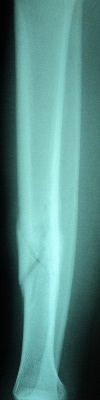

Fraktur tulang adalah cedera serius yang sering terjadi akibat berbagai kecelakaan atau aktivitas fisik yang berlebihan. Identifikasi fraktur tulang dengan cepat dan tepat sangat penting untuk menentukan perawatan yang sesuai. Salah satu pendekatan untuk mengidentifikasi fraktur tulang adalah melalui analisis citra radiografi. Dalam artikel ini, akan dijelaskan bagaimana pengolahan citra, khususnya dengan metode deteksi tepi Canny dan ekstraksi ciri menggunakan metode moment invariant, dapat digunakan untuk identifikasi fraktur tulang tibia dan fibula dengan bantuan algoritma Support Vector Machine (SVM).

Langkah pertama dalam identifikasi fraktur tulang adalah mendapatkan citra radiografi dari daerah yang terkena dampak. Citra radiografi ini biasanya diambil dengan menggunakan peralatan medis yang sesuai.